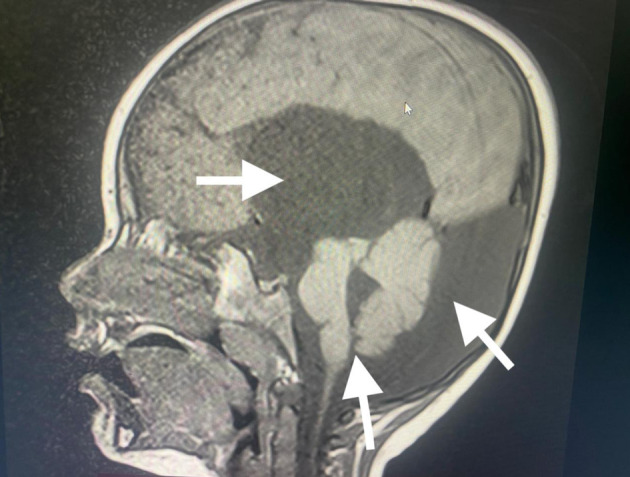

Dandy-Walker综合征是一种罕见的后窝先天性畸形,具有独特的麻醉挑战,包括气道管理困难、意识改变、脑积水和术后通气时间延长的可能性。脑积水是最常见的症状,可使通气和插管复杂化,而脑干受累,以及胼胝体发育不全、脑桥发育不全和髓质呼吸中心扭曲,可能导致术后通气时间延长。这种情况下的麻醉管理需要彻底的气道评估,为潜在的气道困难做准备,颅内压监测和控制,以及全静脉麻醉(TIVA)以促进快速急救。我们描述了一例3岁男性大头畸形、运动障碍、认知发育迟缓和精神状态改变的病例,在没有肌肉松弛剂的情况下,在仔细的气道准备和颅内压控制下,计划在TIVA下放置脑室-腹膜分流术。据我们所知,这是首例用这种方法治疗Dandy-Walker综合征的病例。

Dandy-Walker syndrome is a rare congenital malformation of the posterior fossa that presents unique anesthetic challenges, including difficult airway management, altered consciousness, hydrocephalus, and potential for prolonged postoperative ventilation. Hydrocephalus, the most common finding, can complicate ventilation and intubation, whereas brainstem involvement, along with agenesis of the corpus callosum, pontine hypoplasia, and distortion of the medullary respiratory centers, may contribute to prolonged postoperative ventilation. Anesthetic management in such cases requires thorough airway assessment, preparation for potential airway difficulties, intracranial pressure monitoring and control, and total intravenous anesthesia (TIVA) to facilitate rapid emergence. We describe the case of a 3-year-old male with macrocephaly, movement disorders, delayed cognitive development, and altered mental status, scheduled for ventriculoperitoneal shunt placement under TIVA without muscle relaxants, with careful airway preparation and intracranial pressure control. To our knowledge, this is the first reported case of Dandy-Walker syndrome managed in this manner.